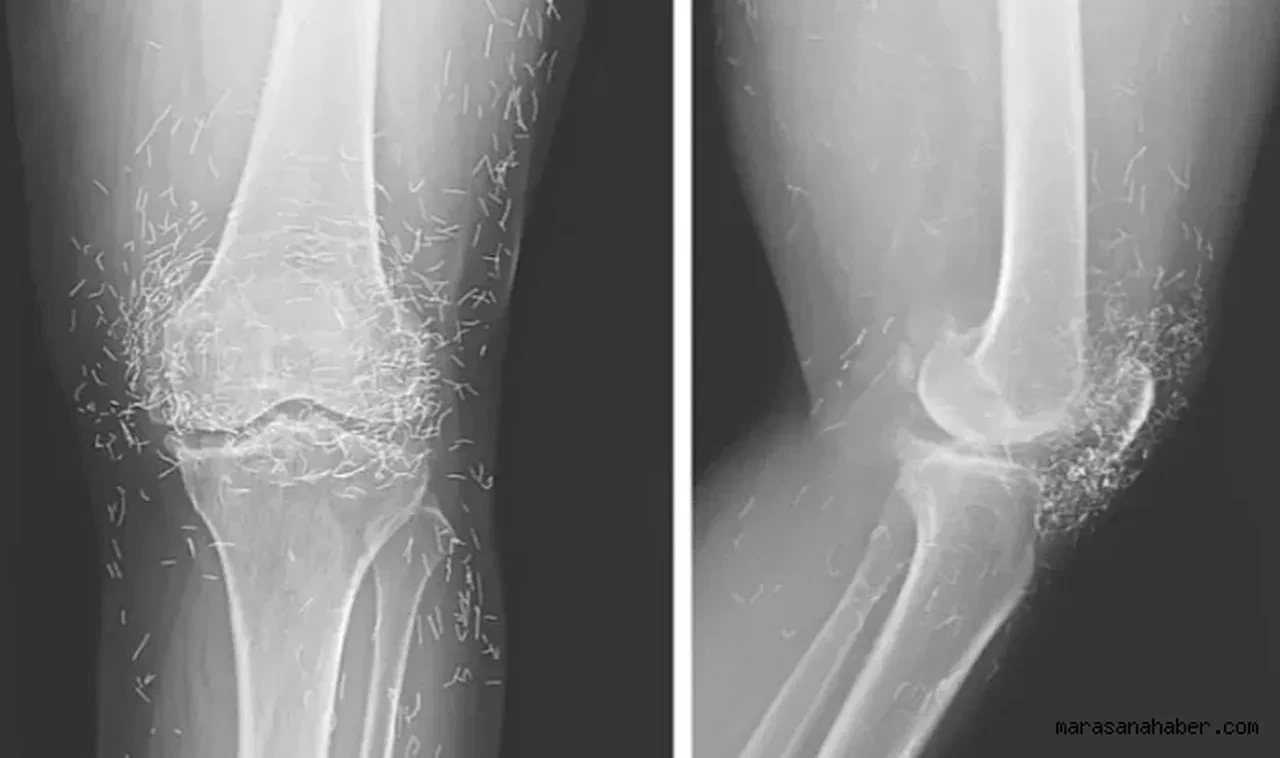

Dizde eklem hastalığı

AKUPUNKTURDA TEDAVİ İÇİN ALTIN İPLİKLER

Dizinde osteoartrit yani kireçlenme bulunan bir kadın, ağrı kesiciler, mide sorunlarına yol açtığı için bıraktı ve akupunktura başladı. Muayene olmak için hastaneye gittiğinde ise eklemlerinde ve kaval kemiklerinde kemik dokusunun kalınlaştığı ve kemik çıkıntılarının oluştuğu görüldü. Ayrıca her iki diz ekleminin etrafında yüzlerce küçük nokta görüldü. Kadının akupunktur uzmanlarının, tedavinin bir parçası olarak kasıtlı olarak dizlerinin içine altın iplikler bıraktığı ortaya çıktı. Başka vakalarda, bu iplikler vücutta yer değiştirdiklerinde kistlere ve doku hasarına neden olabiliyor.